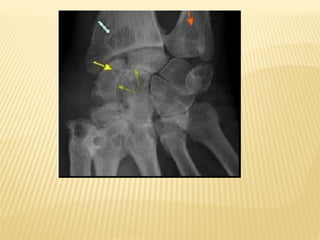

Radiographie d’un genou de face

d’une ostéomyélite subaiguë:

lacune métaphysaire cernée d’os

condensé : abcès de Brodie.